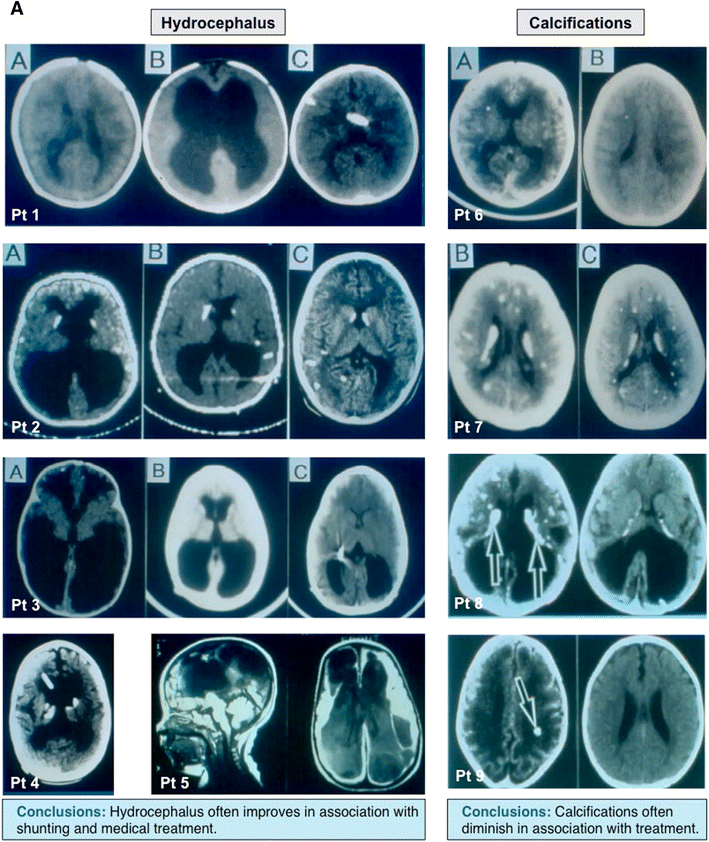

Manifestations of congenital toxoplasmosis and outcomes of treatment. a Neurologic manifestations of congenital toxoplasmosis and response to treatment. Brain CT images depicting the impact of proper shunt placement and treatment of congenital toxoplasmosis on the course of hydrocephalus secondary to T. gondii infection. Adapted with permission from McLeod et al. [207]. b Congenital toxoplasmosis, its impact on the retina, and the effect of treatment on eye lesions. Effect of treatment on the recurrence of eye lesions secondary to T. gondii infection, with increased frequency of occurrence at entrance into school and at adolescence. c Response of active eye lesions to treatment. Treatment of eye lesions leads to resolution of overlying vitritis, hazy margins and sharp demarcation and hyperpigmented lesions. d Choroidal neovascular lesions and their response to anti-T.gondii treatment and antibody to VEGF. The first image is a patient with choroidal neovascular membrane and the resultant resolution with treatment. Note the presence of blood and subretinal fluid, which decreases following treatment with appropriate therapy. Adapted with permission from Benevento, McLeod et al. [206, 207]. Additional choroidal neovascular membranes and their response to treatment in additional patients. The impact of prompt, appropriate treatment of choroidal neovascular membranes in a series of patients. Evidence of bleeding decreases, as does the presence of subretinal fluid in these patients. Adapted with permission from Benevento, McLeod et al. [206]. e Literature outcomes in congenital toxoplasmosis and outcomes in the NCCCTS cohort. A comparison of frequency of outcomes as reported by literature and within the National Collaborative Chicago-based Congenital Toxoplasmosis Study cohort. Note the dramatic decreases in the frequency of outcomes in this particular cohort relative to literature sources. This is true for many outcomes, including IQ, motor function, retinal lesions, and central nervous system manifestations. Adapted with permission from McLeod et al. [206, 207]. f The treatment of congenital toxoplasmosis, in utero, and outcomes due to this early treatment. The impact of treatment, in utero, on the frequency of disease manifestation in congenital T. gondii infection. Note the increased frequency of most disease manifestations without the initiation of treatment, in utero. Adapted with permission from and McLeod et al. [207]. g Parasite serotype and its relationship to treatment efficacy. Tabular representation of the impact of parasite type on outcomes in treated patients. Postnatal treatment was effective (i.e., improved outcomes) in both type II and type NE-II parasites, indicating that both respond to treatment. Adapted with permission from and McLeod et al. [207]. h Outcomes in NCCCTS cohort compared to the literature. Data indicating improved outcomes in treated patients over preexisting literature data on pre-established endpoints, including neurologic outcomes, reductions in IQ, worsened vision, new retinal lesions, and hearing loss. Adapted with permission from McLeod et al. [206, 207]. (I) Dosage of Pyrimethamine and its Impact on Treatment Outcomes. Kaplan–Meier plots indicating no significant differences in outcomes between two treatment arms receiving higher doses of Pyrimethamine versus lower doses. In practice, infants with less severe manifestations often receive the lower dose of Pyrimethamine, though with severe disease often are still treated with higher doses. Adapted with permission from McLeod et al. [206, 207]

Many children born with congenital toxoplasmosis who are treated in utero and throughout the first year of life have normal cognitive development and function well, being able to continue on to university and having families of their own. There is more retinal disease among children born in the USA who missed being treated in utero and appears to occur more often in those who were not diagnosed and treated in the first year of life. There is a gradation in outcomes from severe impairment to completely functional children and young adults, both with and without treatment in the first year of life. It appears that outcomes with treatment for those who are born with moderate or severe involvement at birth are markedly better than that reported in the older literature for those who were not treated or treated for only 1 month [43, 44, 62, 64, 65, 69, 81••]. Approximately 70 % of children who had generalized systemic or neurologic manifestations and thus would have been expected to have severe disability have done well. Interestingly, for treated children, intracerebral calcifications may resolve partially or completely during the first year of life [90]. However, there may also be significant impairment. Severe involvement may impact quality of life when treatment is started too late to effect a markedly improved outcome [174].